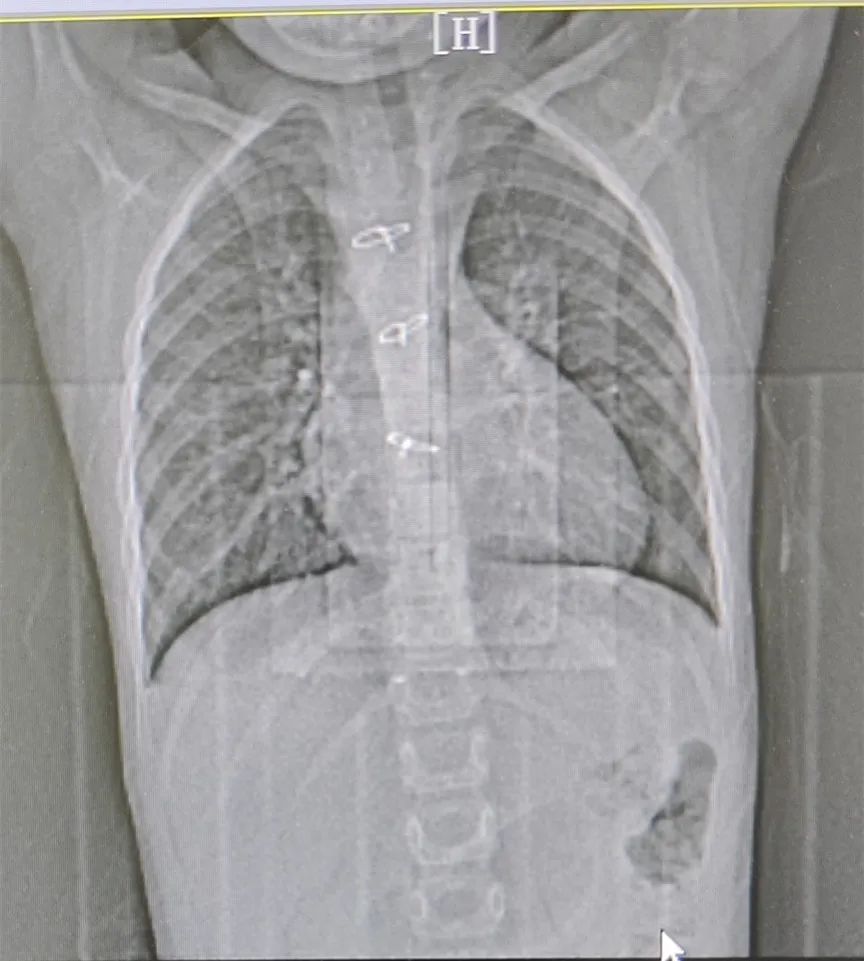

术前胸部 CT 平扫